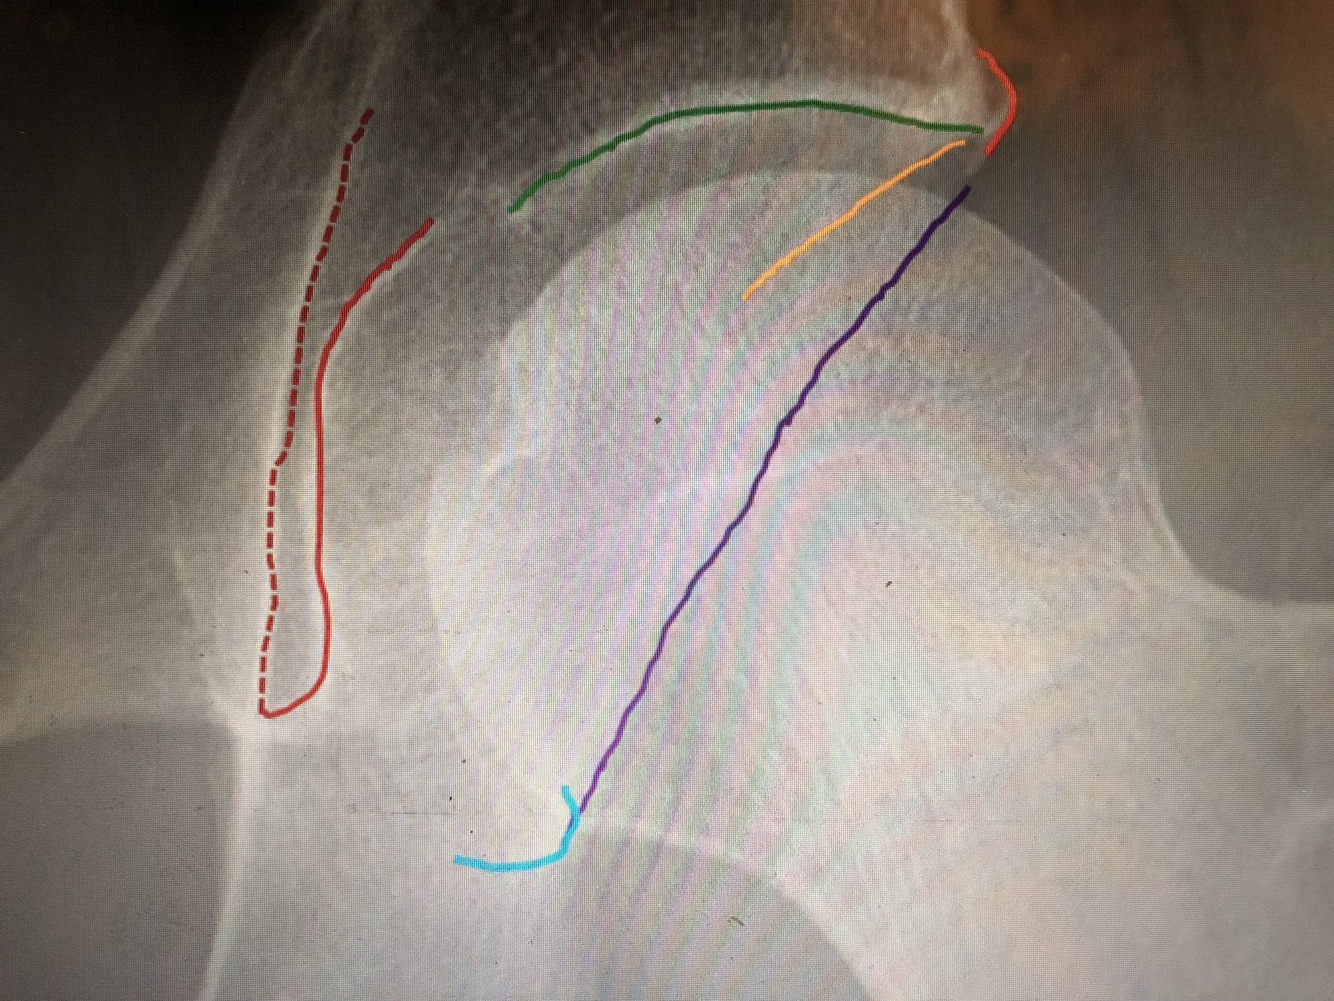

What is the red line?

most lateral part of Kohler’steardrop is the medial margin of the acetabulum

What is the green line?

The superior portion of the acetabulum has the thickest cortex

What is the orange line?

Superolateral margin of the acetabulum

What is the blue line?

Inferior portion of the acetabulum

What is the purple line?

The posterior rim of the acetabulum is more lateral.

What is the yellow line?

The anterior rim of the acetabulum is more medial. (not completely seen)